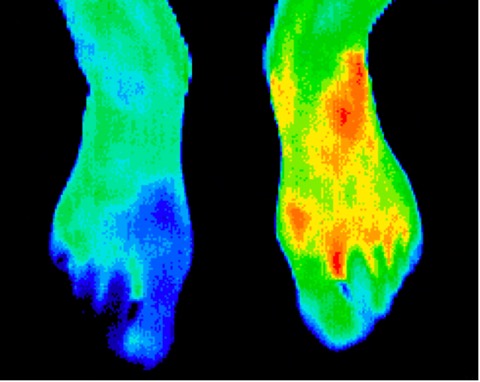

Right foot reflex sympathetic dystrophy